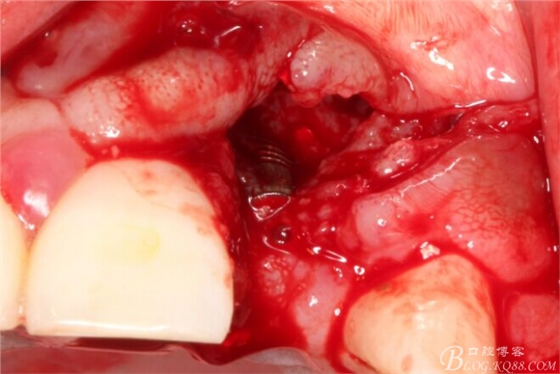

于是我果斷告知患者,手術(shù)失敗了,不能拖延,如不及時(shí)處理,炎癥繼續(xù)發(fā)展會(huì)很快波及鄰牙牙槽骨。患者接受我的建議。切開翻瓣,骨粉及生物膜消失了,骨吸收嚴(yán)重,幸運(yùn)的是,因?yàn)樘幚砑皶r(shí),鄰牙骨支持依然存在。

徹底掻刮。